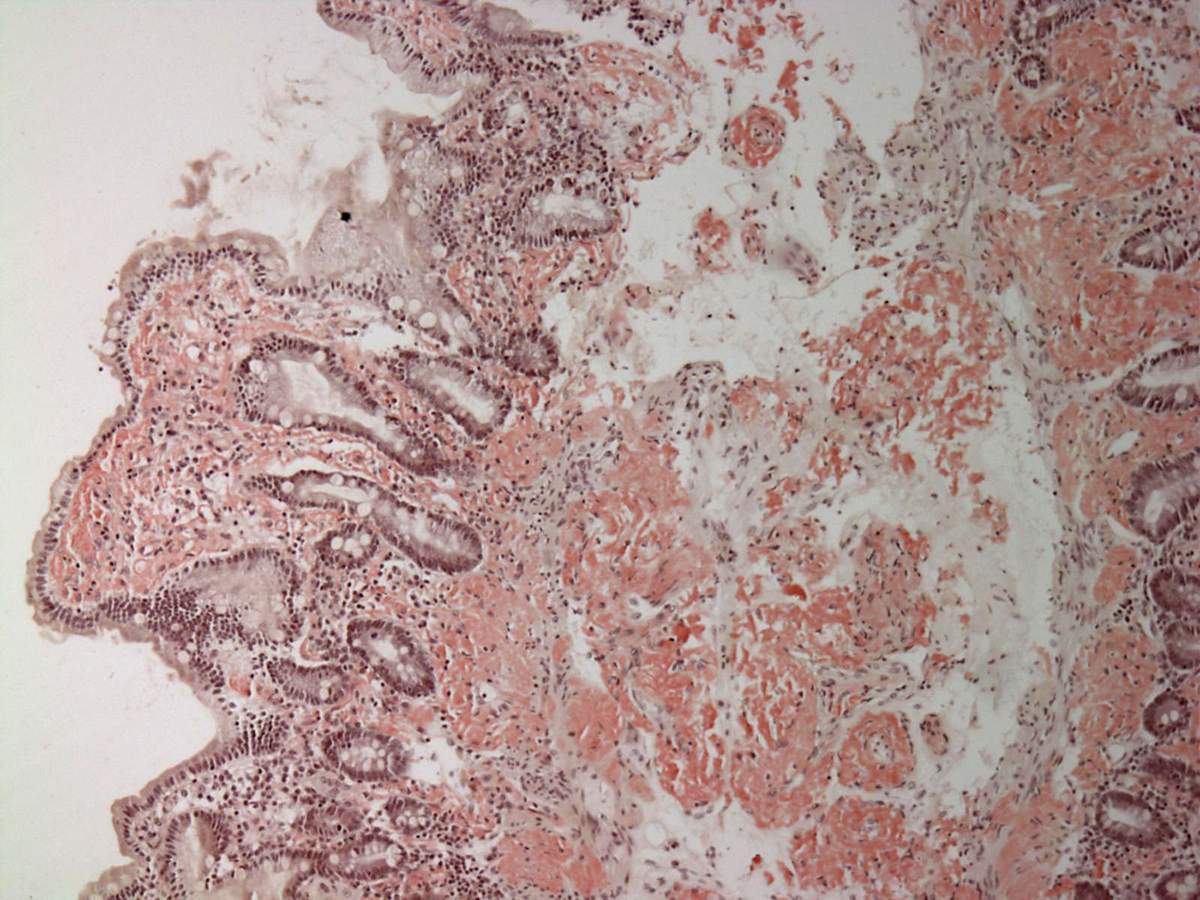

Амилоидоз кишечника - заболевание кишечника (самостоятельное заболевание или «вторая болезнь»), обусловленное отложением в его тканях амилоида.

При амилоидозе может поражаться весь желудочно-кишечный тракт, но наиболее значительное отложение амилоида происходит в тонком кишечнике.

Развитие амилоидоза связано с нарушением белково-синтетической функции ретикуло-эндотелиальной системы, накоплением в плазме крови аномальных белков, служащих аутоантигенами и вызывающих образование аутоантител. В результате взаимодействия антигена с антителом происходит осаждение грубодисперсных белков, участвующих в образовании амилоида. Откладываясь в тканях (например, в стенках сосудов, железистых ), амилоид вытесняет функционально специализированные элементы органа, что ведёт к гибели этого органа.